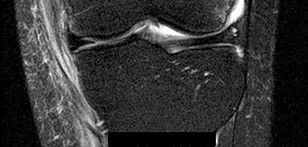

A 68-year-old female is evaluated 6 weeks after an uncomplicated primary total knee arthroplasty (TKA). Despite dedicated daily physical therapy, her range of motion remains stalled at 10 to 70 degrees. Radiographs reveal well-fixed and well-aligned components without signs of loosening. What is the most appropriate next step in her management?

Explanation

Postoperative stiffness after TKA is a well-recognized complication. The optimal timing for manipulation under anesthesia (MUA) is generally between 6 to 12 weeks postoperatively when conservative measures (aggressive PT) have plateaued or failed. Performing an MUA within this window is highly effective for breaking up immature adhesions. Waiting beyond 12 weeks decreases the success rate due to the maturation of dense intra-articular scar tissue.